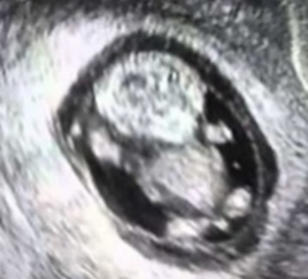

本来、ママの子宮はまぁるい形(写真左)が理想です。赤ちゃんは生まれてからの準備を、すでにお腹の中にいるときから頑張っています。これがまん丸が崩れたような形(写真右)ですと赤ちゃんも頑張りづらいのです。